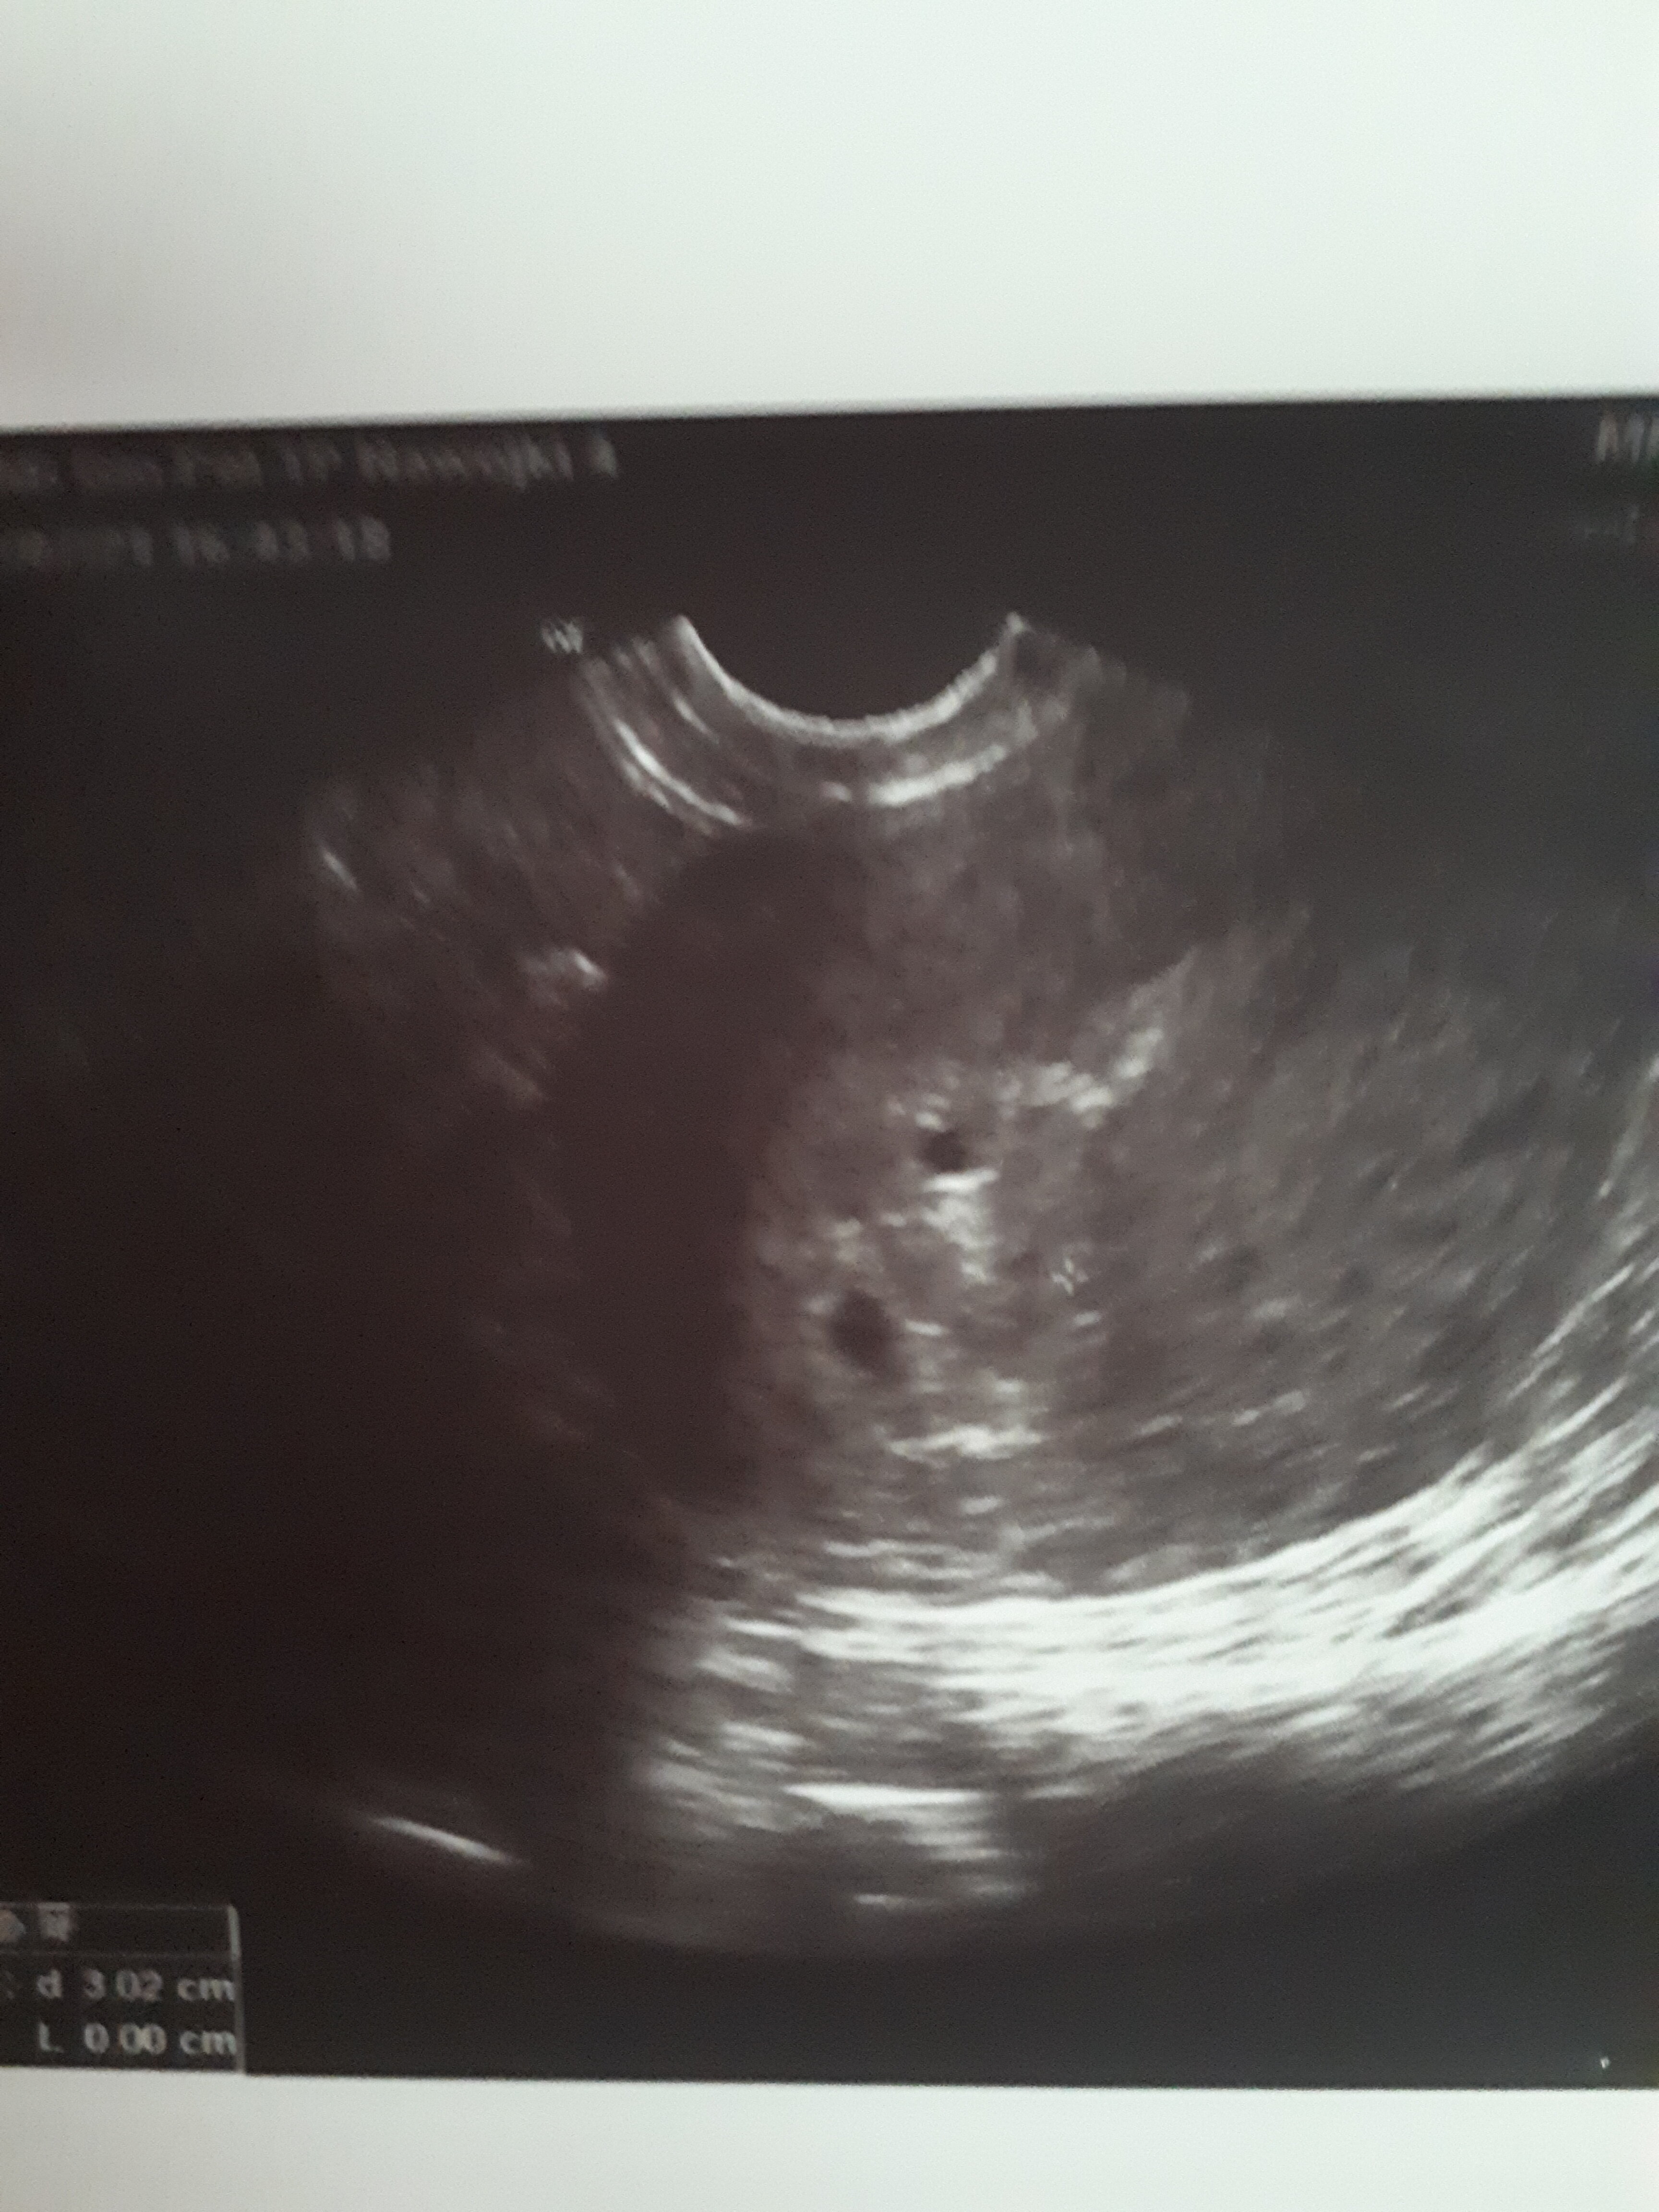

Jestem w ciąży, jakoś 6 tydzień (trudno podać dokładnie, bo mam długie cykle). W zeszłym tygodniu na usg widoczne były dwa pęcherzyki- jeden większy, drugi mniejszy. Początkowo lekarz podejrzewał ciążę mnogą.

Dziś byłam drugi raz (dopiero dziś się zorientowałam, że jakość sprzętu jest tragiczna), Pan obejrzał jeden pecherzyk- biło już serce (ja ledwo dostrzegłam rozmazane piksele). Zapytałam czy jedno, był zaskoczony moim pytaniem. Zapytałam o ten drugi pecherzyk, który dziś też dostrzegłam- większy niż ostatnio, powiedział, że to bez znaczenia. Al jak dopytywalam co to jest- od niechcenia rzucil- powietrze.

Też mi przyszlo do głowy, że to nic dobrego.. Ale na sprzęt bym nie zwalała- bo wwygląda jak pęcherzyk ciążowy, jest tylko trochę mniejszy.. Ale na pewno się powiększył od ostatniego badania, podobnie jak ciążowy..

Z wczorajszego badania mam ujęte tylko jednen pęcherzyk, a to zdjęcie sprzed tygodnia.

Ten niżej to pecherzyk ciążowy, w nim biło serce, a ten drugi, nawet nie specjalnie obejrzany przez lekarza, jest wyżej- jakby z tylu..

Nie wiem, co myslec- podejrzewałam, że już wczoraj zobaczę tylko jeden pecherzyk z serduszkiem i tyle. Ale ten drugi się powiększył.. Gdyby się wchłaniał to powinien być mniejszy..